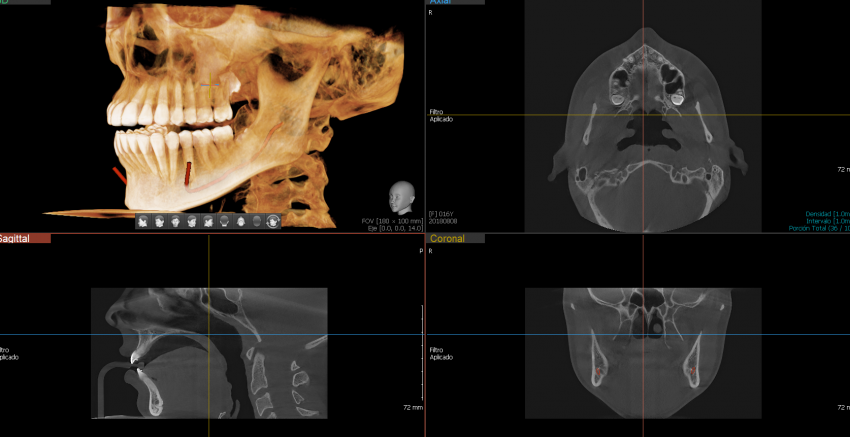

Green 16/18 ofrece una gama de campos de visión seleccionables. Multi FOV permite al usuario seleccionar el modo FOV óptimo y minimizar la exposición a áreas que no son la región de interés. Seleccione el tamaño adecuado de FOV entre 16×9/18×10, 12×9/13×10, 8×9 y 5×5 basado en una particular necesidad de diagnóstico.

Cubre la región del arco completo, seno y la ATM izquierda / derecha y es adecuado para la mayoría de los casos de cirugía oral así como la cirugía de implantes múltiples. También puede medir el volumen de la vía aérea.